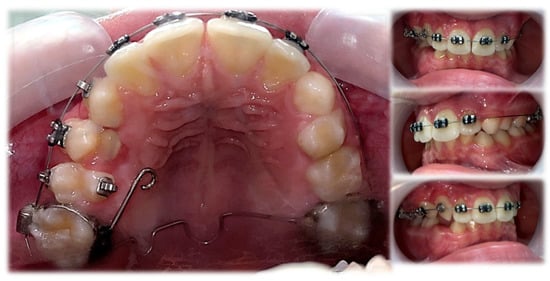

The initial orthodontic treatment plan required modification. Primarily, it was assumed that the traction of 13 would be required. This meant the need for the surgical exposure of the 13 crown, bonding of the attachment to the enamel surface and the application of an orthodontic fixed appliance in the upper dental arch. However, regular observations of 13 movement led to anticipating a spontaneous eruption on the condition that it would not be hindered by the malposition of Teeth 14 and 15. For this reason, the surgical exposure was unfounded. The aim of further orthodontic procedures was a distal movement of 14 and 15, to release the 13 eruption path. This was performed by an initial alignment with the aid of a specially designed transpalatal arch. On the right side, palatally from the first molar, an additional loop and a hook were added to a wire to enable the attachment of the elastic chain and provide a force to derotate the upper right second premolar (Figure 12). Subsequently, an attempt of derotation and alignment of the upper right first premolar was undertaken. However, due to the severe vestibuloposiotion of 14 and unfavorable alveolar boundary conditions, cautious orthodontic mechanics were required. Informed consent was obtained with notification of a possible revision in the treatment plan in case of a necessity to extract 14. The next step was a preadjusted fixed appliance therapy (MBT prescription, slot 0.022″) starting with a light continuous NiTi wire and continuing with a typical wire sequence and sliding mechanics (Figure 13).

Figure 13.

Treatment progress.